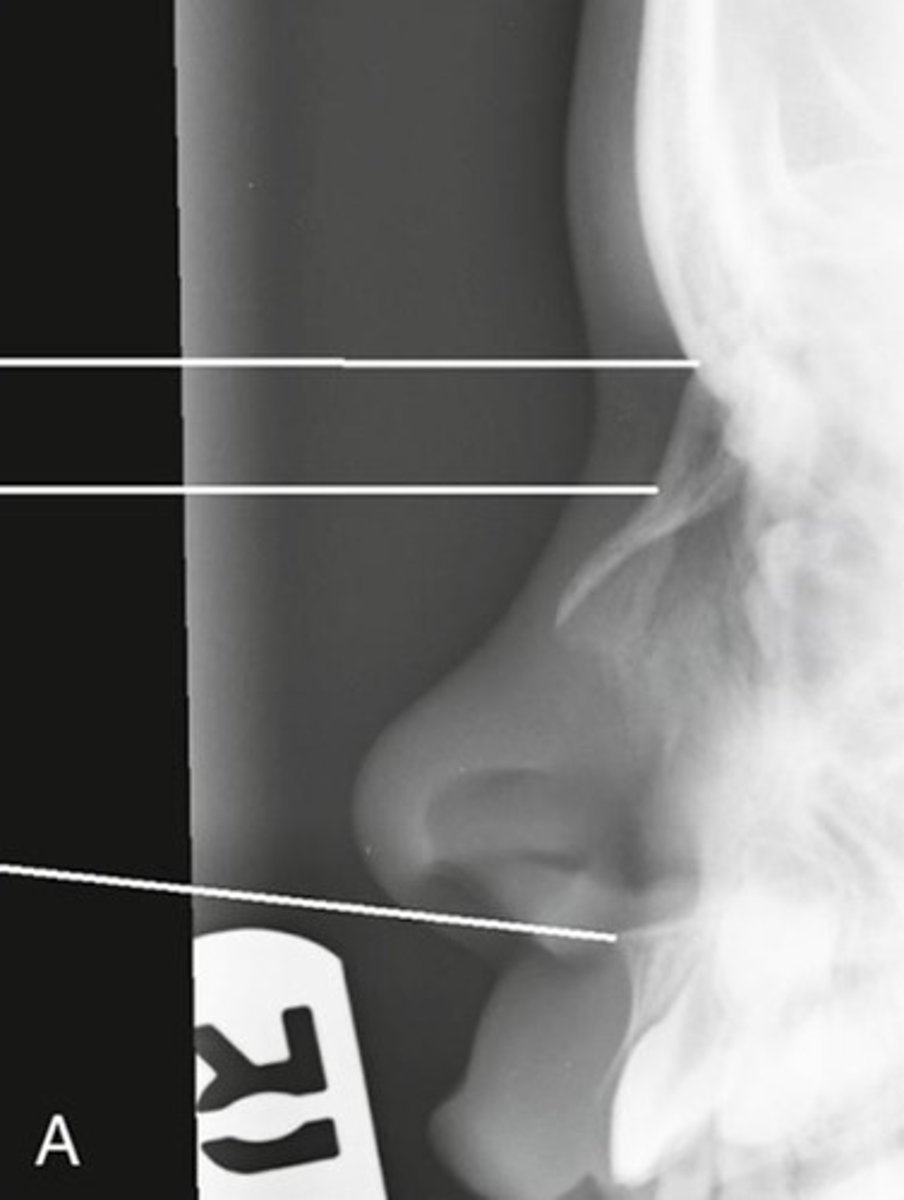

What projection and anatomy is demonstrated?

PA of the mandibular body